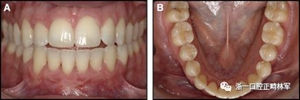

正畸文獻閱讀--固定舌側保持器作用下意外的牙齒移動

圖4柔軟的螺旋弓絲保持器,下頜右側尖牙嚴重的舌側傾斜以及下頜左側尖牙的唇側移位:A,正面視圖; B,咬合面視圖(John Iaculli博士提供)。